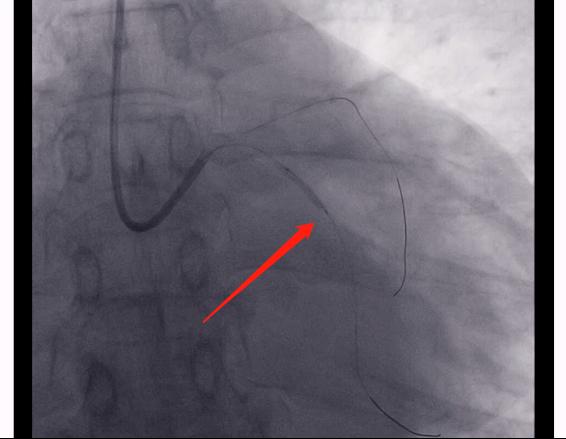

如图,是右侧的冠脉造影。

病人的右冠也是闭塞的,并且一开始就闭掉了。

导丝

4.对于冠心病患者,我们只有进行规范化的、综合性的康复的治疗,才会有一个良好的结果。(图片是患者打通闭塞血管,放置了两根支架的一个情况。同时我们还可以看到右边这根血管闭塞出现的一个侧枝循环,也就是左侧的这些血管,和右侧血管远端联通的一个影像,这就是自身进行的侧支循环的建立。)